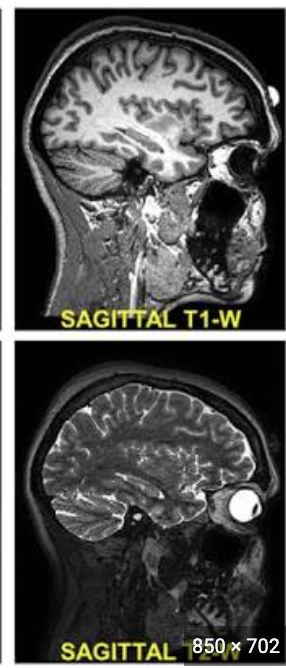

What is MRI?

A cross-sectional imaging technique using a magnetic field and radiofrequency signals to generate images from hydrogen nuclei in water molecules

How are sagittal MRI images viewed?

From one side of the body to the other

How are axial MRI images viewed?

From the feet toward the head like CT

What are the two common MRI sequences?

T1-weighted and T2-weighted

What is a basic tenet of MRI?

Define anatomy (T1)

Detect abnormal fluid (T2)

Hint: H2O → T2

White = edema in photo

How does water or edema usually appear on T2-weighted MRI?

Bright